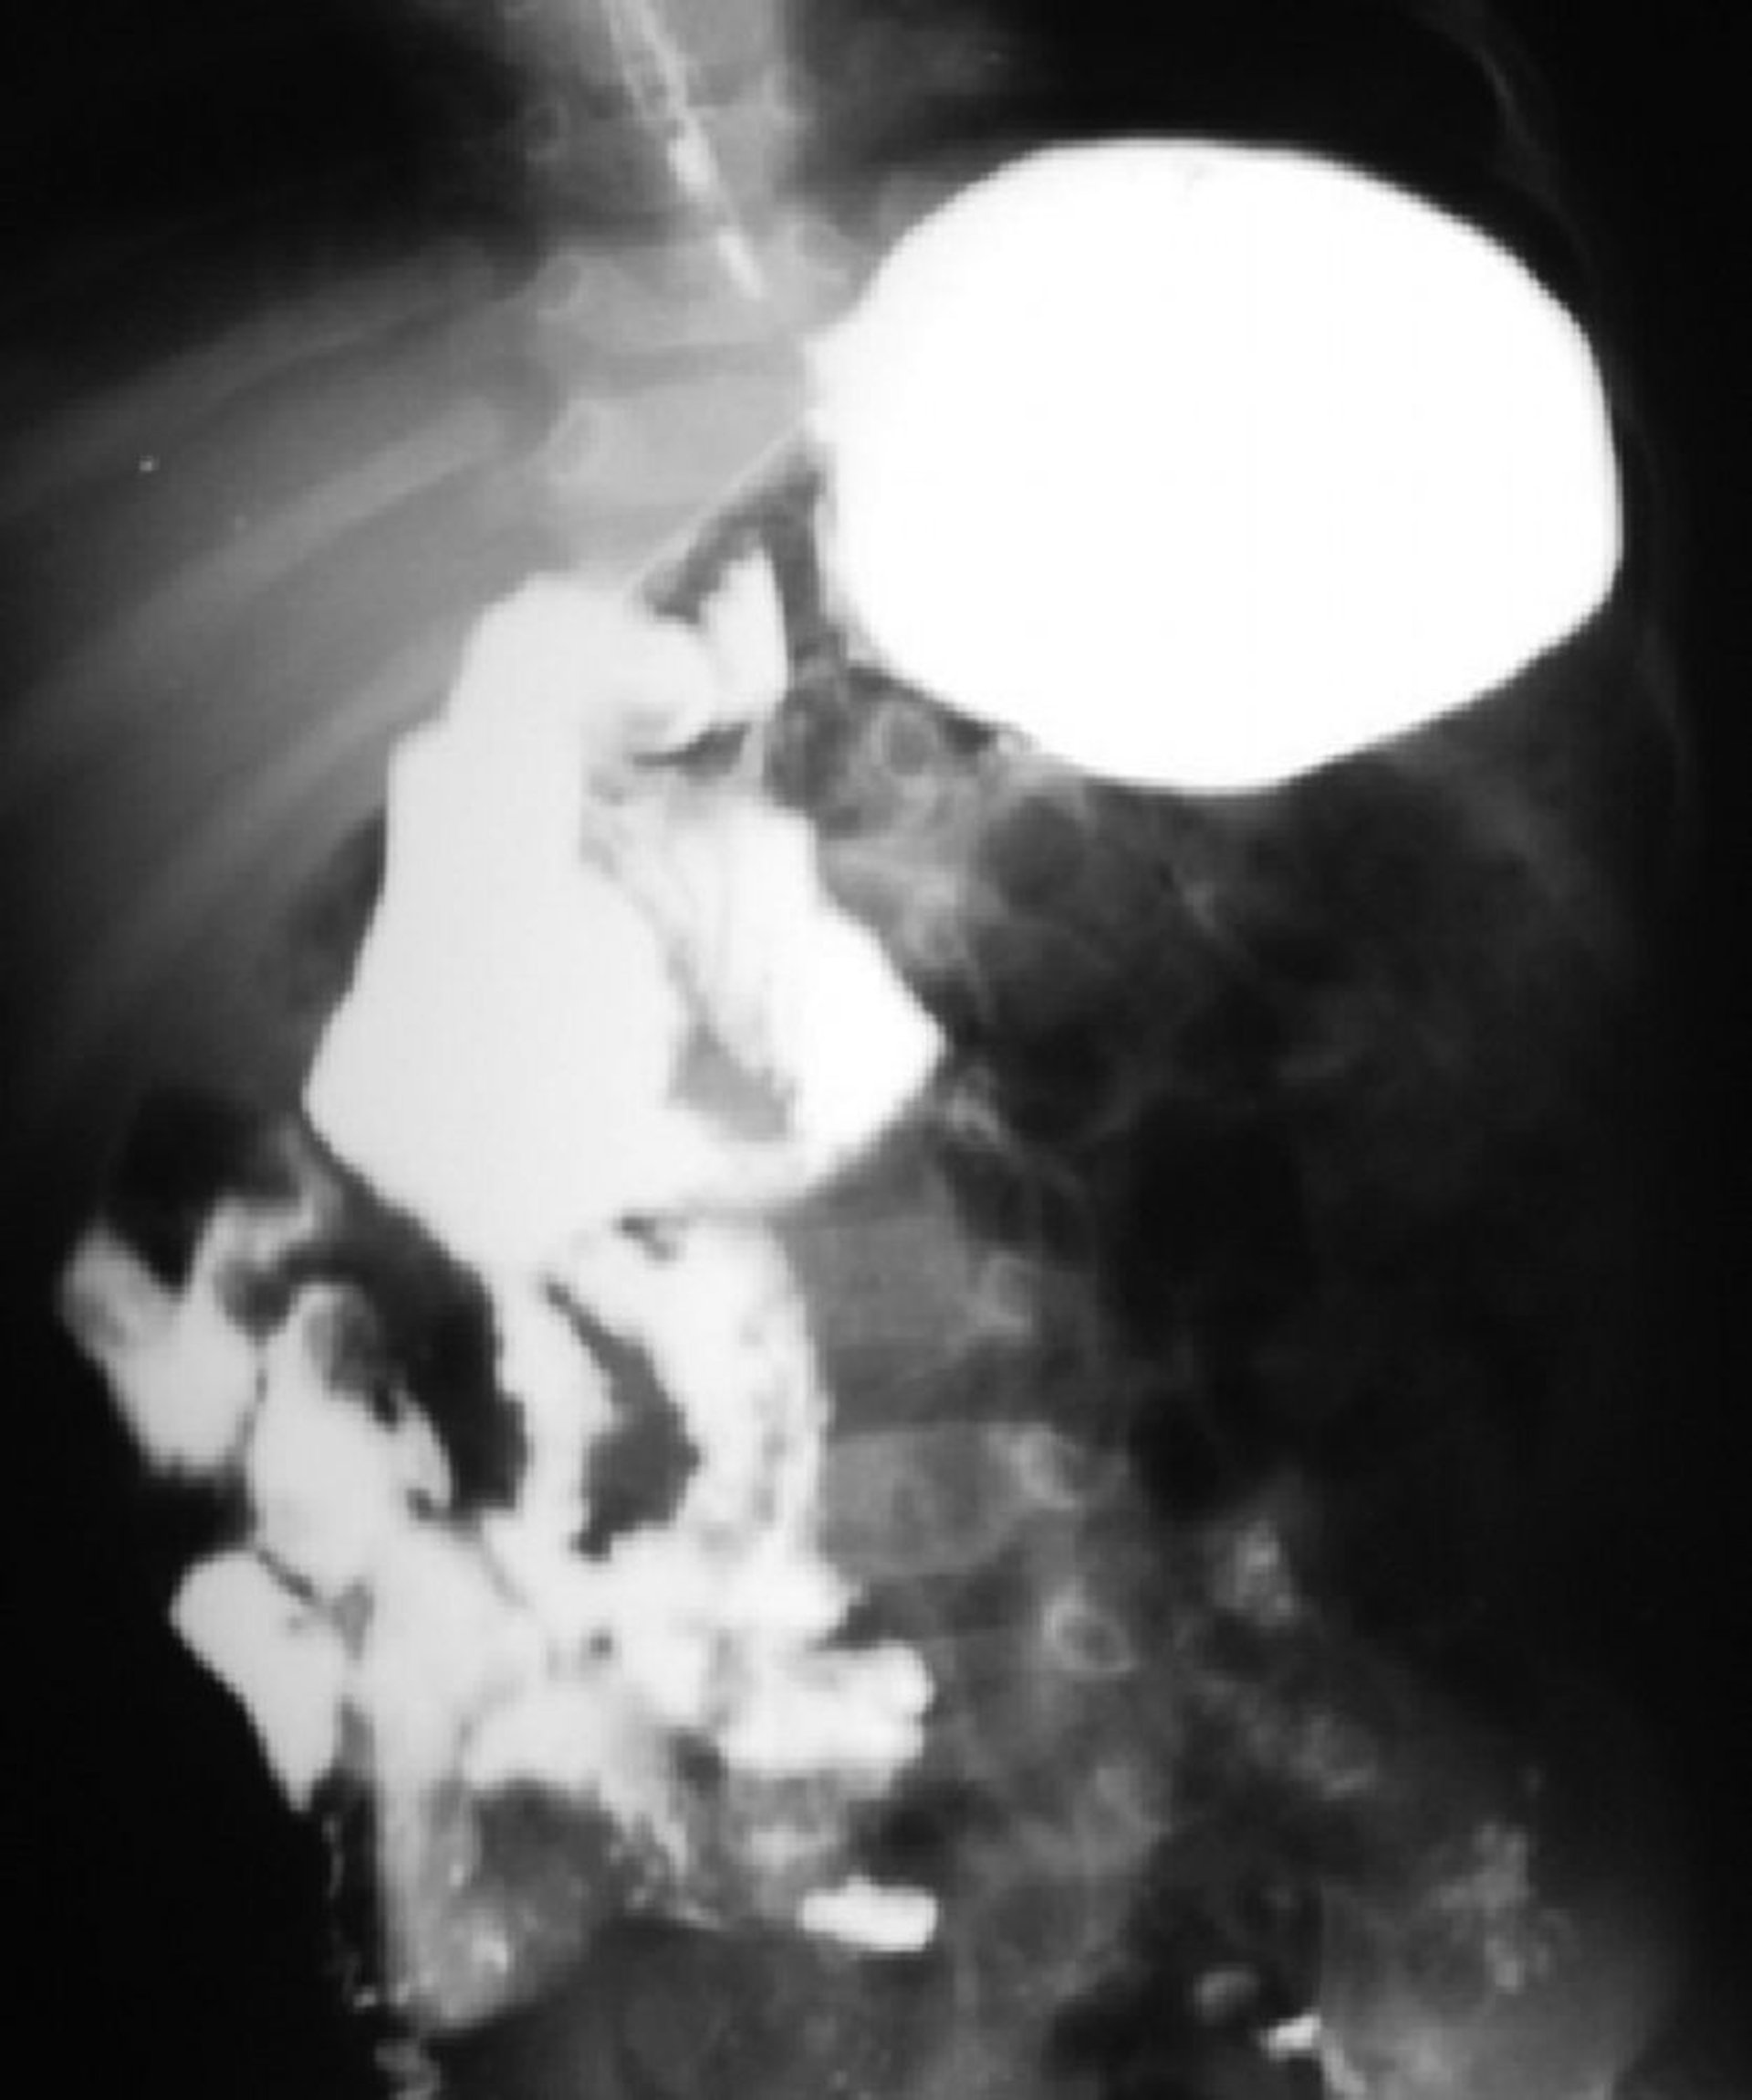

Malrotation intestinale

Cette examen baryté montre une malrotation de l'intestin. La jonction duodénojéjunale est située du côté droit de la colonne vertébrale et la majeure partie de l'intestin grêle est du côté droit.